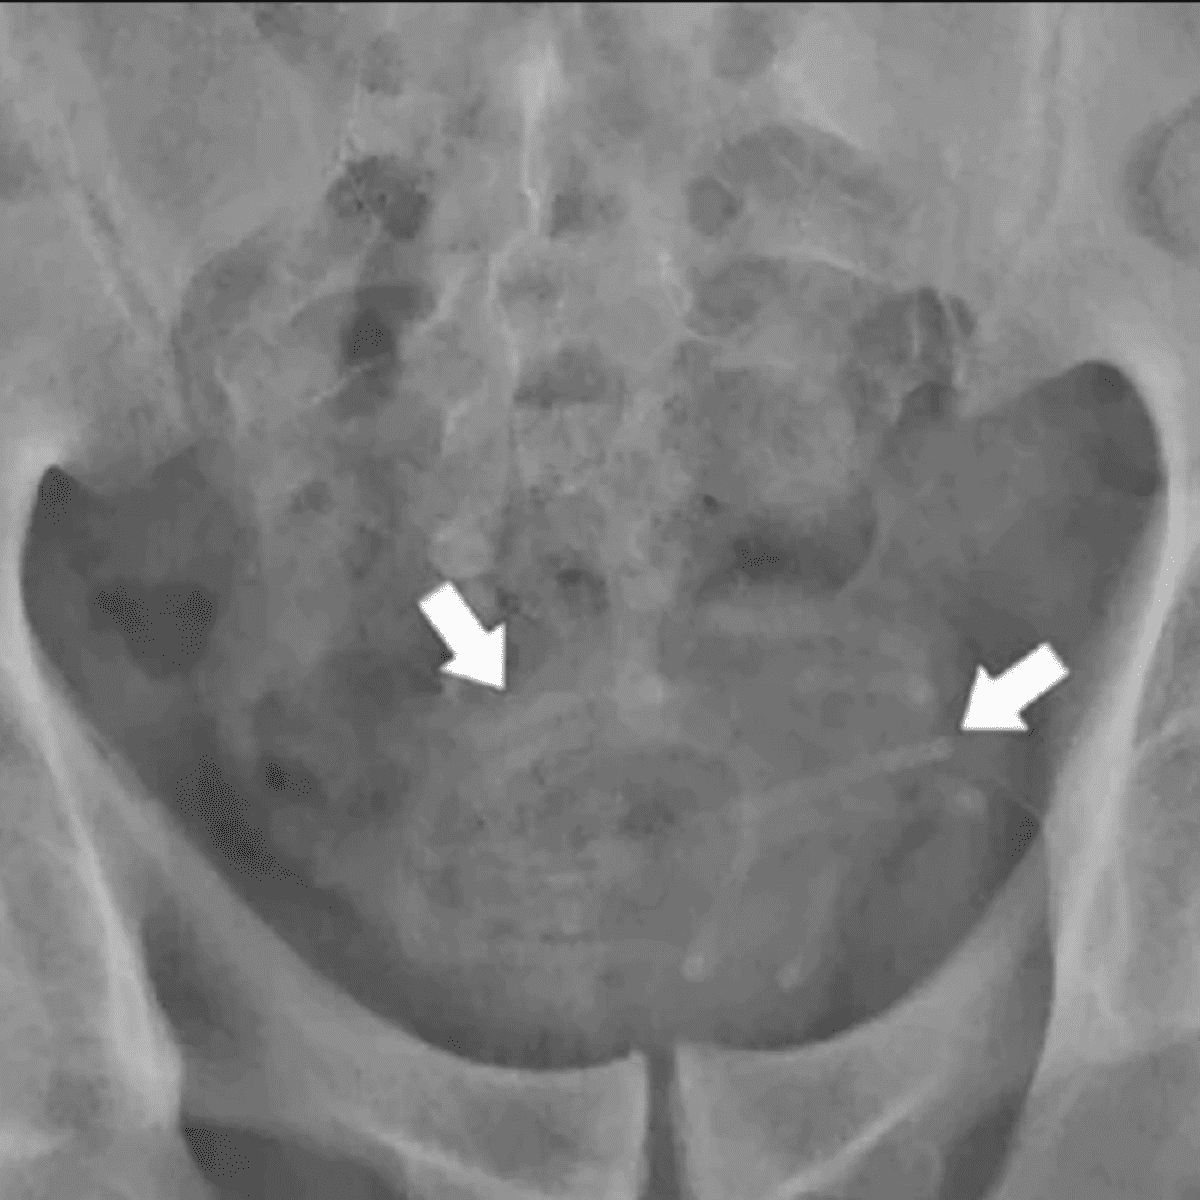

La historia no termina acá, ya que el hombre luego admitió que los auriculares llegaron ahí debido a una particular práctica sexual. Los mismos médicos del lugar quedaron completamente sorprendidos al ver la radiografía.

Al ver los auriculares en la vejiga, los médicos actuaron de inmediato para quitárselos cuanto antes. Para poder llevar a cabo la extracción, debieron utilizar unas pinzas especiales, y de esta manera, lograron descubrir que se trataba de unos cables de un ancho de 0,15 centímetros, y una longitud de 78cm.